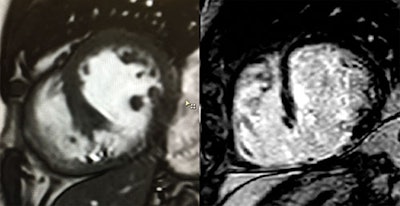

A 67-year-old male patient was referred for assessment of viability following recent acute myocardial infarction. A still frame of a midventricular short-axis cine (left) and a late gadolinium-enhanced MRI scan in the same orientation (right) are shown.

By Drs. Sebastian Onciul and Sven Plein, University of Leeds, U.K.